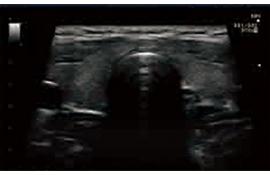

斑點智能抑制

自動識別和強化回聲信號中有效的組織特征信息,抑制并濾除噪聲,

提高信噪比,使圖像更清晰通透。